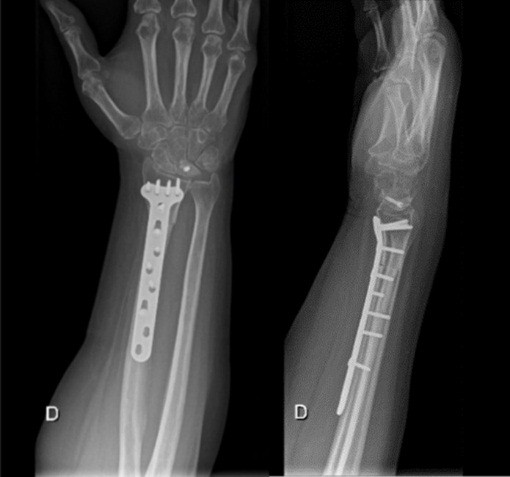

Both patients were positioned in the supine position, and a tourniquet was inflated to 250 mmHg at the start of the procedure. The surgical technique involved a closing wedge osteotomy of the radius combined with compression screw fixation to stabilize the lunate fracture. For osteotomy stabilization, a T-plate was applied to the distal radius: a palmar approach following Henry’s technique was used for Patient A, whereas a dorsal approach centered on the third ray was employed for Patient B. The lunate fracture was stabilized using a cannulated compression screw: A SpeedTip 2.2 mm Medartis screw (Fig. 7) for Patient A and an HCS 2.4 mm compression screw (Fig. 8) for Patient B.

Figure 7: Patient A – post surgery.

Figure 8: Patient B – post surgery.

The mean follow-up duration was 24 months (Patient A: 36 months and Patient B: 12 months). Bone consolidation of the radial osteotomy was achieved on average 3 months postoperatively for both patients, while consolidation of the lunate fracture occurred at 6 months for Patient A (Fig. 9) and at 7 months for Patient B (Fig. 10). Lunate fracture union and radial osteotomy union were assessed with CT.

The distal radius plate was removed due to discomfort at 13 months for Patient A and at 3 months for Patient B.